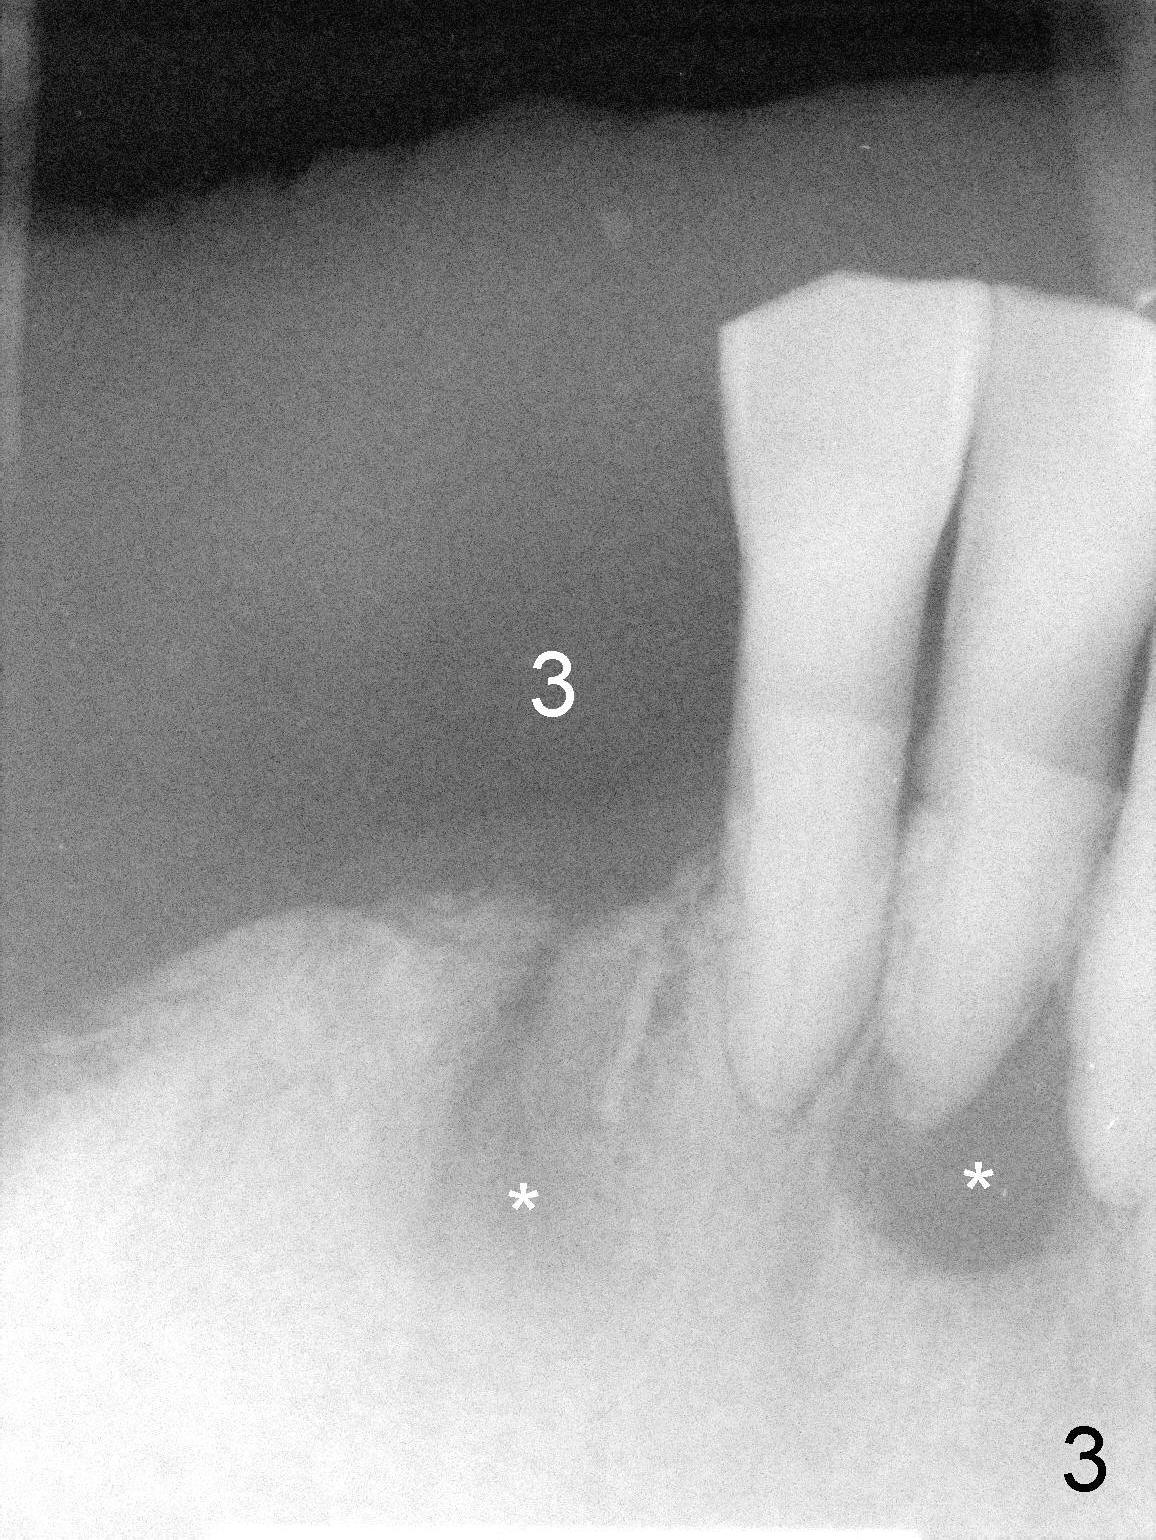

The lower right bridge (from canine (Fig.2: 3) to 1st molar (Fig.1: 6)) fails while a 77-year-old man is undergoing chemotherapy for urinary bladder cancer. The abutments of the bridge are extracted without plan for implants (Fig.4). Four months later, the patient returns for implants (Fig.3), but the ridge is narrow (Fig.5). While 2 of 3x14 mm 1-piece implant are placed at the canine and 1st bicuspid sites, 2 piece ones at the 2nd bicuspid and 1st molar sites (Fig.6: 3.5x11 mm, 5x14 mm). Soft (Fig.7-10) and hard (Fig.11) tissues heal 1 week (Fig.7) and 4 months (Fig.8-11). There is minimal bone resorption 1 year 7 months post cementation (Fig.12,13, non-splinting). It appears that narrow diameter implants are a valid solution to narrow ridge at the sites of the lower canine and premolar. As long as there are enough implants for function, the crowns are not necessary to be splinted. Surprisingly, the patient starts flossing after implant restoration. Retrospectively an immediate provisional bridge should have been fabricated.

There appears to be no bone loss 2 years 5 months post cementation (Fig.14). Gingival bands form around the implants at #27-29 three years 1 month post cementation (Fig.15 *).